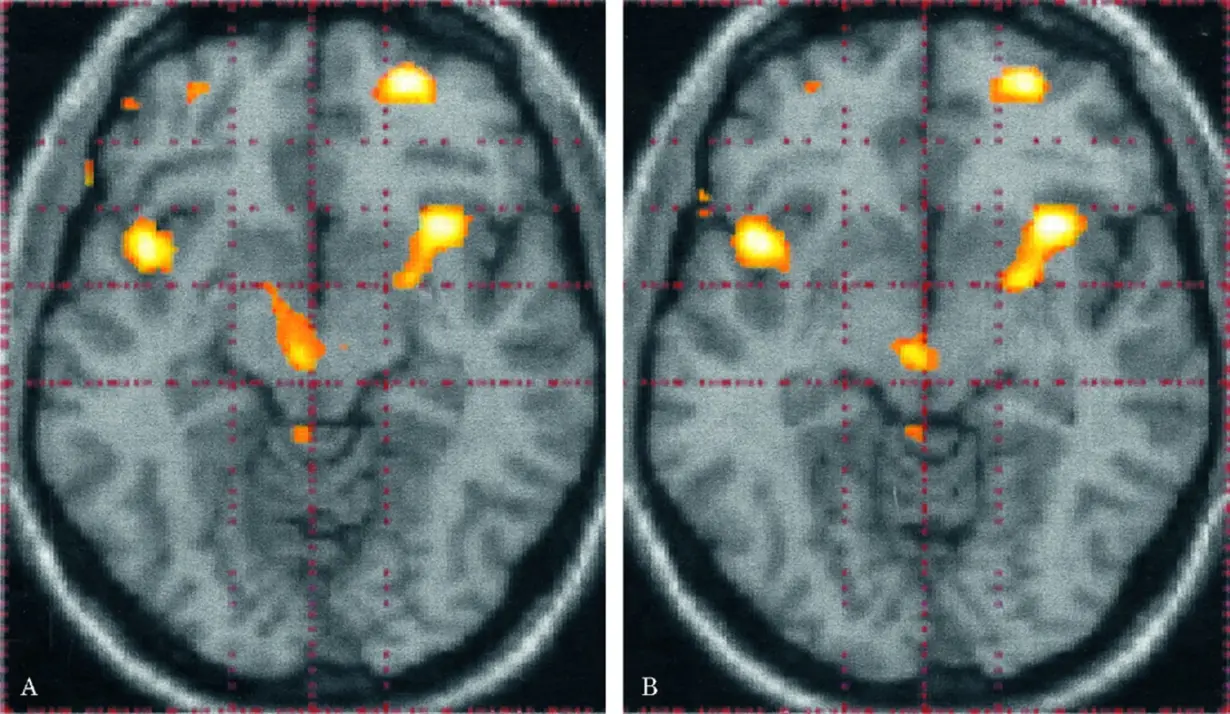

Neural networks underlying magnitude perception: a specific meta-analysis of fMRI studies

Hazal Şimşek-Ünver , Burcu Sırmatel-Bakrıyanık , Beyza Doğanay , Fuat Balcı , Metehan Çiçek

Cerebral Cortex, Volume 35, Issue 7, July 2025

Neural networks underlying magnitude perception: a specif ic meta-analysis of fMRI studies

Cerebral Cortex, Volume 35, Issue 7, July 2025, bhaf163.